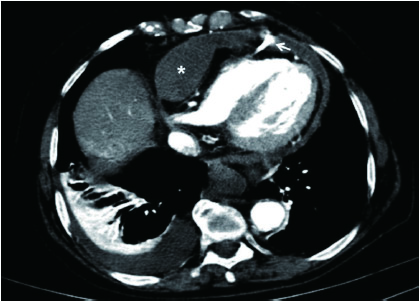

血液透析隧道导管右心室穿孔1例